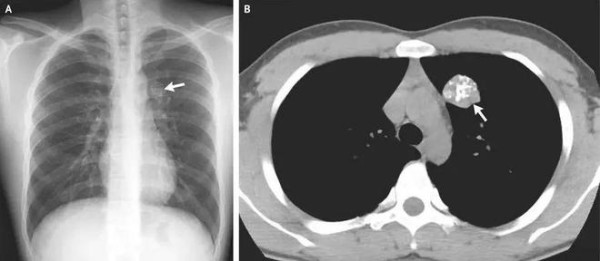

事实上,在X线片、 CT、钼靶、超声报告中,常常会出现“钙化”“钙化灶”的字样。据生命时报,钙化,指人体内的钙离子以磷酸盐或碳酸盐形式,发生沉积的过程。很多钙化是在人体病变修复过程中形成的,整个过程和伤口愈合结疤类似。通常表现为钙盐沉积在受损组织中,使这些组织变得坚硬。

人体绝大部分组织和器官内都可能出现钙化,比如头颅的脑膜、基底节区,胸部的肺、肋软骨、胸骨剑突,腹部的肝脏、肾脏,以及甲状腺、乳腺和前列腺等腺体,还有遍布身体的大多数动脉和静脉血管。钙化存在的广泛性也使得它成为体检和平时检查中影像学报告上的“常客”。